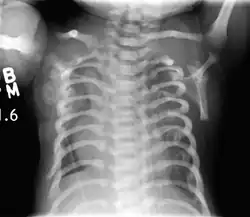

| CXR of a newborn with asphyxiating thoracic dysplasia. Note the short ribs. | |

Asphyxiating thoracic dysplasia (ATD), also known as Jeune syndrome, is a rare inherited bone growth disorder (autosomal recessive skeletal dysplasia) [1] that primarily affects the thoracic region. It was first described in 1955 by the French pediatrician Mathis Jeune.[2] Common signs and symptoms can include a narrow chest, short ribs, shortened bones in the arms and legs, short stature, and extra fingers and toes (polydactyly). The restricted growth and expansion of the lungs caused by this disorder results in life-threatening breathing difficulties; occurring in 1 in every 100,000-130,000 live births in the United States.[1][3]

Jeune syndrome is a rare genetic disorder that affects the way a child's cartilage and bones develop. It begins before the child is born and primarily affects the child's rib cage, pelvis, arms and legs.[5] Usually, problems with the rib cage cause the most serious health problems for children with Jeune syndrome. Their rib cages (thorax) are smaller and narrower than usual, which inhibits the child's lungs from developing fully or expanding when they inhale. The child may breathe rapidly and shallowly. They may have trouble breathing when they have an upper or lower respiratory infection, like pneumonia. Breathing trouble can range from mild to severe. In some children, it is not noticeable, aside from fast breathing; however, in others, breathing problems can be fatal. About 60% to 70% of children with this condition die from respiratory failure as babies or young children. Children with Jeune syndrome who survive often develop problems with their kidneys, and over time they may experience kidney failure.[2] As a result, few children with Jeune syndrome live into their teen years. Children with Jeune syndrome have a form of dwarfism. They are short in stature, and their arms and legs are shorter than most people's.[6]

Jeune syndrome is a rare autosomal recessive ciliopathy.[7] This diagnosis is grouped with other chest problems called thoracic insufficiency syndrome (TIS). Diagnosis of Jeune syndrome can be made as early as before birth if signs and symptoms are apparent on an ultrasound; however, diagnosis after birth usually occurs through X-rays and genetic testing, such as the tests found on the Genetic Testing Registry (GTR).[8]